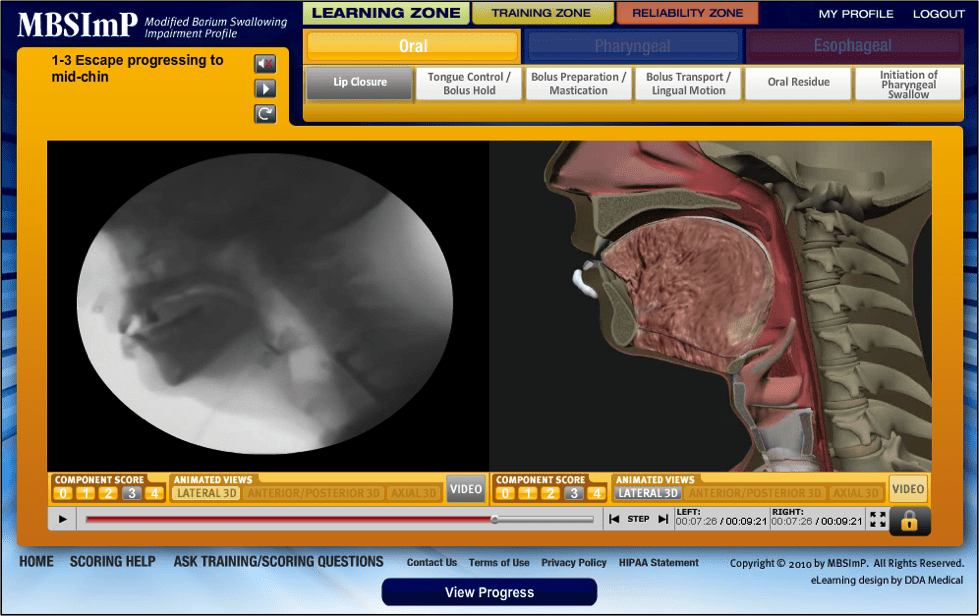

MBSImP Bonnie Martin-Harris